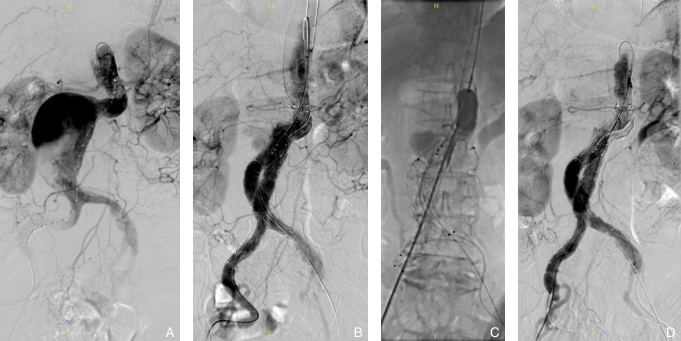

图1 术中Ⅰ a型内漏的处理 A:基线造影可见瘤颈扭曲,预估Ⅰa型内漏风险高,利用push-up技术释放主体并预留导丝;B:标准EVAR完成后可见Ⅰa型内漏;C:通过预留导丝跟进导管于瘤颈处,球囊阻断后注射蛋白粘合剂;D:Ⅰa型内漏消失Fig.1 Intraoperative management of type Ia endoleak A: Baseline angiography shows a tortuous aneurysm neck with a high predicted risk of type Ia endoleak, and the main body stent graft is deployed using the push-up technique with a guidewire intentionally retained; B: Completion angiography after standard EVAR reveals the presence of a type Ia endoleak; C: A catheter is advanced along the retained guidewire to the aneurysm neck, and fibrin glue is injected following temporary balloon occlusion; D: The type Ia endoleak is completely resolved